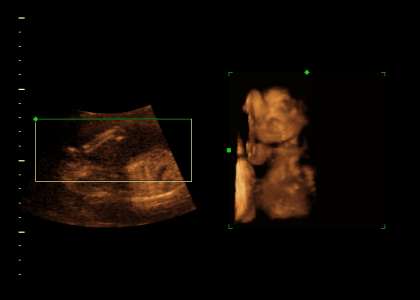

Standart & 3D Ultraschall... (2)

Ultraschall / 3D